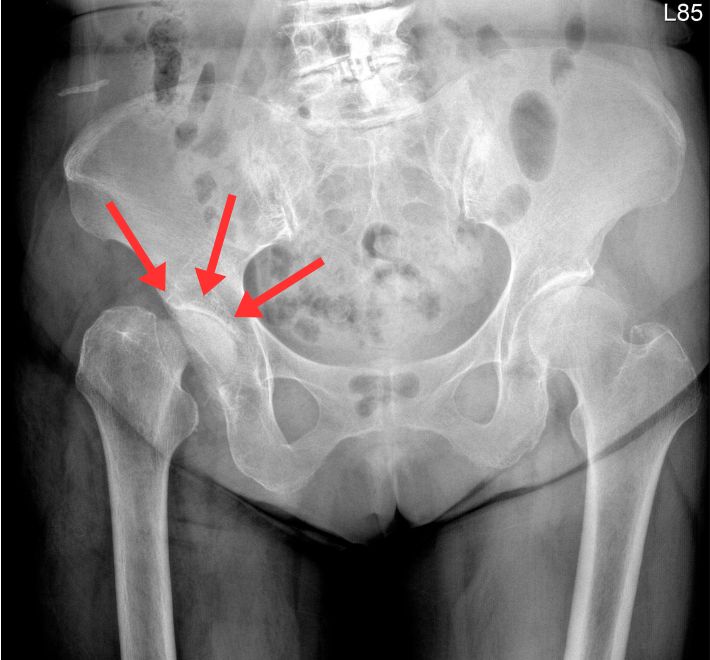

3. 長短腳與跛行

當單側髖關節嚴重退化、軟骨消失甚至骨頭變形時,患者的骨盆會產生代償性傾斜,視覺上呈現「長短腳」。 長期下來,這不僅會導致走路跛行,更會進一步引發腰椎側彎與對側膝關節的退化。

髖關節退化分期:您在哪個階段?

退化性髖關節炎在臨床上,我們常參考 Kellgren-Lawrence (K-L) 分級系統,這有助於患者理解為何醫師建議特定治療:

後期(第 4 級)

關節間隙幾乎消失,骨頭與骨頭直接磨擦,出現囊腫與硬化。此時生活品質嚴重受損,通常是微創髖關節手術的最佳介入時機。

精準診斷是成功治療的關鍵

張建鈞醫師團隊強調,所有成功的醫療介入都奠基於 「精準診斷」。

-

影像學評估:透過 X 光檢查關節間隙,並進一步運用 核磁共振 (MRI) 或 電腦斷層 (CT) 判斷骨密度 (BMD) 與軟組織受損程度。